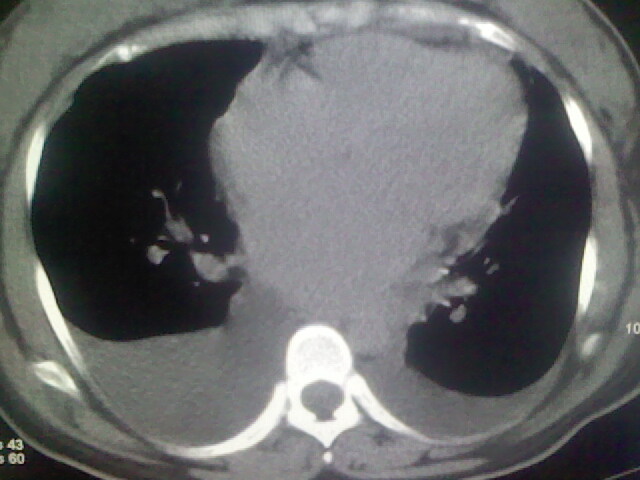

女,24,剖腹产后,突觉胸痛,干咳,不能平卧

双肺“肺泡性肺水肿” “胸腔积液”!

考虑肺梗塞、肺水肿,双侧胸腔积液

肝脾大,双侧胸腔积液,双肺水肿,肺动脉[包括远端小动脉],左右心房,左心室增宽,右心室主动脉无明显改变,符合左心功能不全征;;建议除外二尖瓣关闭不全,扩张性心肌病

考虑产后心肌病,心功能不全,肺水肿,双侧胸腔积液。